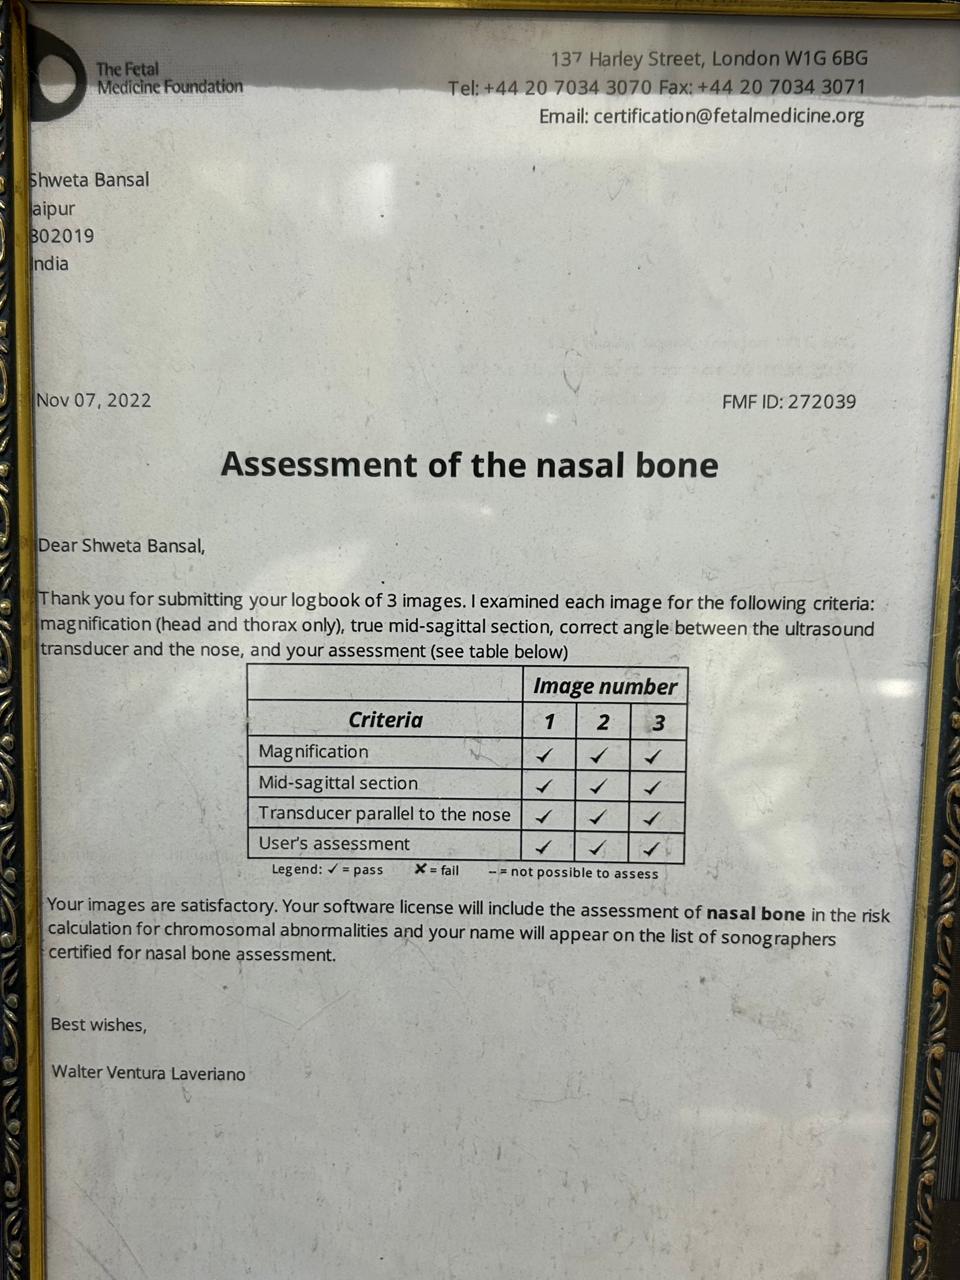

Dr. Shweta Diagnostic & Child Care Centre

Expert Care in Fetal Medicine, Pediatrics & Diagnostics

Your trusted destination for compassionate and advanced healthcare — from pregnancy to childhood and beyond. We specialize in fetal medicine, pediatric care, and precision diagnostics, all under one roof for your family’s complete wellness.